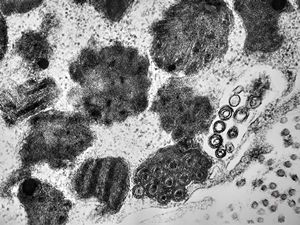

M,1y. | unusually cup-shaped mitochondria - plexus papilloma

M,1y. | intramitochondrial inclusion - plexus papilloma